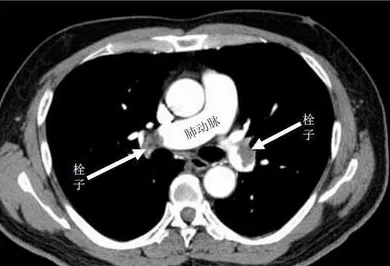

什么是急性肺栓塞?为何如此凶险?

急性肺栓塞是血栓堵塞肺部血管导致的急症,起病急、进展快,死亡率极高。患者常表现为突发的呼吸困难、胸痛、血氧下降,严重时可瞬间致命。溶栓治疗是通过药物快速溶解血栓,恢复肺部血流的关键手段,但需严格把握“黄金时间窗”。